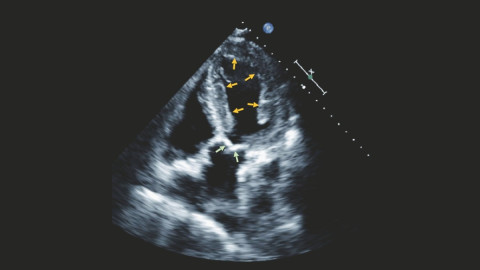

Zweidimensionale Echokardiographie in der Diastole (wenn die Herzkammer entspannt ist).

© Udo Sechtem (Zweidimensionale Echokardiographie) Patient mit kardialer ATTR-Amyloidose: Die gelben Pfeile zeigen auf den rundum verdickten Muskel der li. Herzkammer; Aortenklappe (hellgrüne Pfeile) ist verdickt.